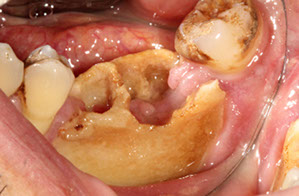

Dentigerous Cyst

- aka follicular cyst, odontogenic cyst

2nd MCC of odontogenic cyst (~1/5 epithelium-lined jaw cysts), and the MCC of developmental odontogenic cyst; usually in young adults and teens

- assoc c crown of an unerupted (or partially erupted) tooth, usually the mandibular third molars (wisdom teeth)

- thought that the pressure from an erupting tooth on the follicle obstructs venous flow and causes an exudate to form bwt the reduced enamel epithelium and the tooth crown

- multiple simultaneous cysts are uncommon

- may be found on radiographs taken for delayed tooth rupture; usually painless, can be painful if infected; can be large enough to displace involved teeth and cause resorption of adjacent teeth

Imaging: usually a well-defined, unilocular radiolucency on X-ray c sclerotic rim (can look the same as KCOT and ameloblastoma)

Micro: cyst cavity lined by stratified squamous epithelial cells from reduced enamel epithelium of the tooth forming organ

- has no rete ridges, flat interface, lining epithelium 2-4 layers of cuboidal epithelium

DDx: Cystic ameloblastoma (usually has reverse polarization of nuclei [away from BM]); KCOT (has hyperchromatic basal palisading of cuboidal / columnar cells, and wavy surface parakeratosis)

Px: excellent, almost never recur c complete enucleation

Dentigerous cyst lined b thin layer of stratified squames c chronic inflam in stroma